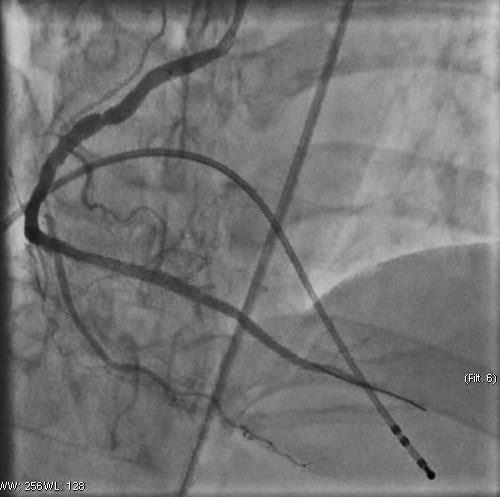

Ê - kíp can thiệp đã tiến hành đặt máy tạo nhịp tim cho người bệnh và đặt 1 stent vào vị trí bị tắc. Sau khi can thiệp đặt stent, động mạch vành đã được tái thông - Ảnh BVCC

Có lại nhịp tim mới chỉ là bước đầu. Tình trạng của người bệnh vẫn đang “ngàn cân treo sợi tóc” vì nguyên nhân gây ngừng tim là do nhồi máu cơ tim vẫn còn đó, tim có thể tiếp tục ngừng đập bất kỳ lúc nào. Người bệnh nhanh chóng được chuyển vào phòng can thiệp tim mạch để chụp và can thiệp mạch vành tái thông mạch vành bị tắc.

Tại phòng can thiệp các bác sĩ đã tiến hành Chụp động mạch vành cho kết quả: động mạch vành phải bị tắc hoàn toàn. Do thời gian ngừng tuần hoàn quá dài, người bệnh rơi vào tình trạng suy đa tạng, tình trạng sốc tim và rối loạn nhịp tim vẫn còn. Sau can thiệp, người bệnh được chuyển về Khoa Hồi sức tích cực – Chống độc để điều trị hồi sức chuyên sâu.